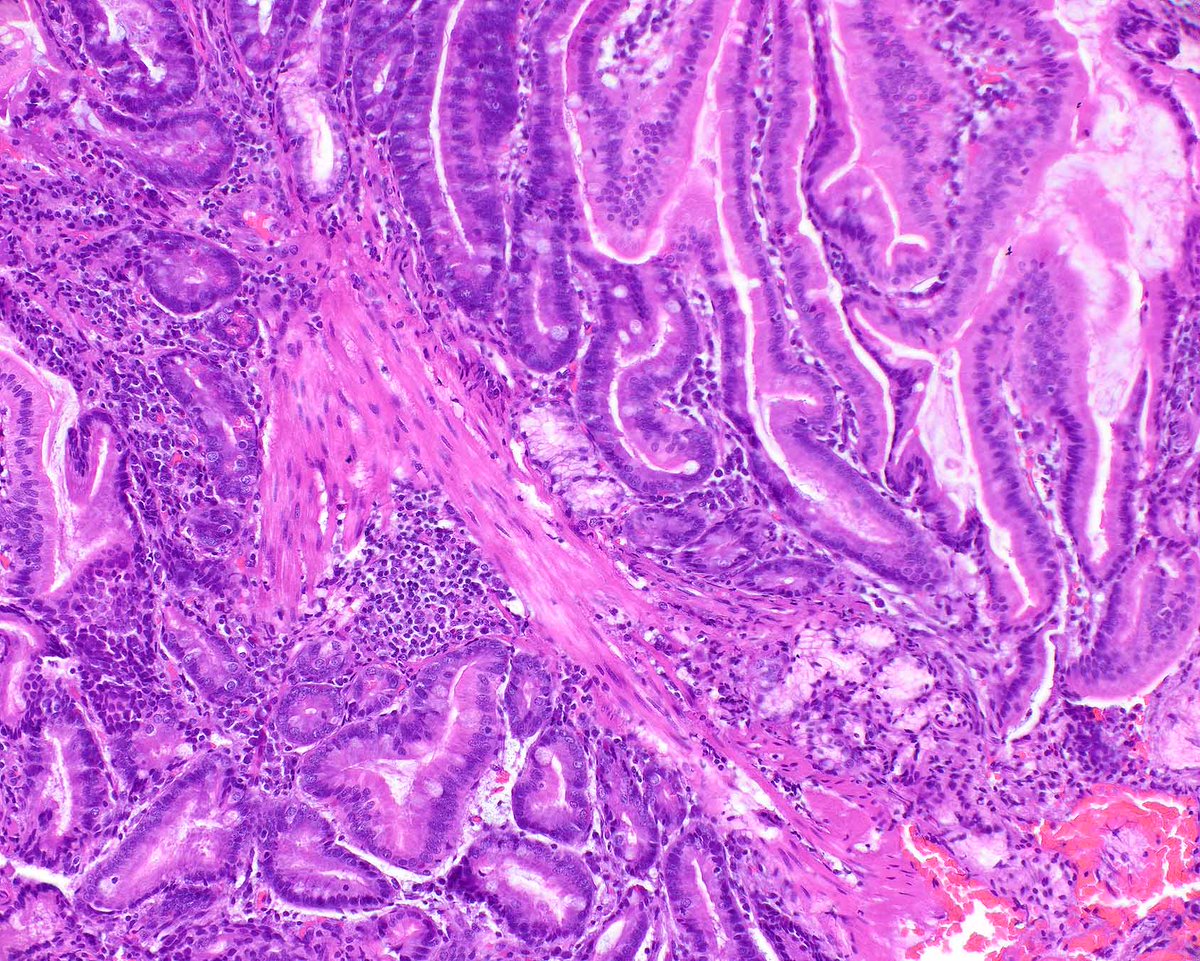

Esophageal inflammatory fibroid polyps are rare and benign. They are generally submucosal-based but this one extended into the lamina propria. PMID: 39259144